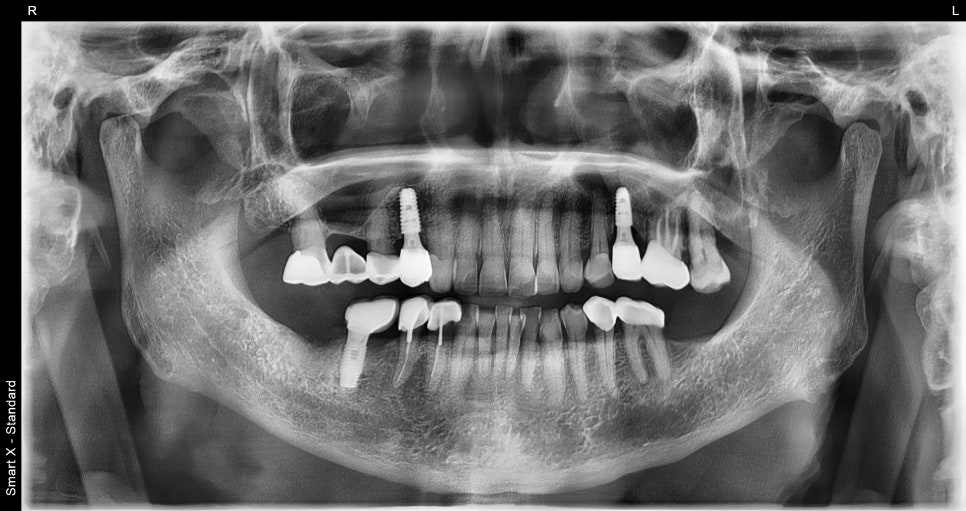

– 유착 확인 후 지대주 연결 → 최종 보철물 장착 → 교합 조정으로 마무리했습니다.

✔️ 양쪽 어금니로 균형 있게 씹을 수 있어 식사 효율이 향상되었습니다.

✔️ 턱관절 통증도 많이 완화되어 전반적인 삶의 질이 크게 향상되었어요.